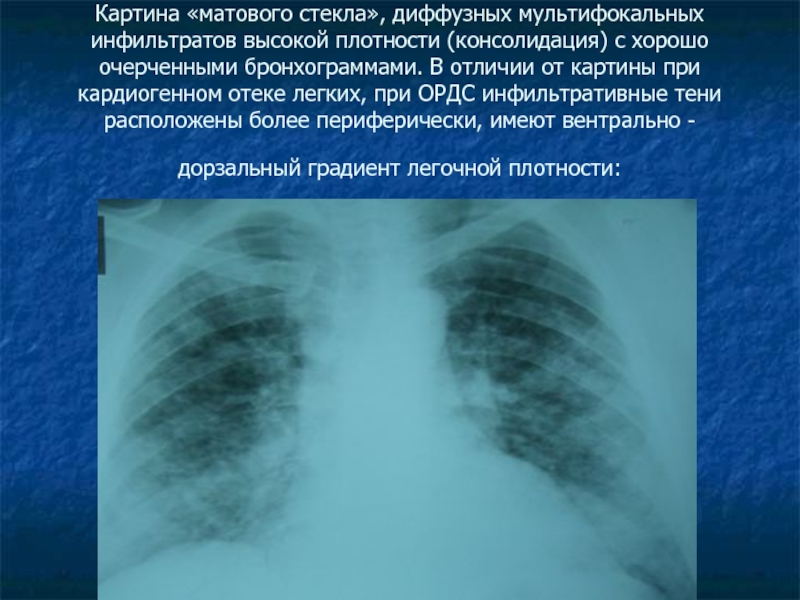

Рентгеновские снимки при пневмоцистной пневмонии